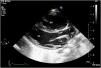

A 10-day-old term neonate with tachypnea and peripheral oxygen saturation of 90% was referred to us with a diagnosis of transposition of the great arteries with intact ventricular septum for early arterial switch operation. The child weighed 2.8 kg and was not dysmorphic. Precordial examination revealed cardiomegaly, loud second sound and a grade 2 mid-systolic murmur in the upper left sternal border. Clinical examination and transthoracic echocardiography suggested usual arrangement of the visceroatrial structures and normal leftward cardiac apex. Systemic and pulmonary venous drainage were normal. A stretched open foramen ovale shunted right-to-left. The atrioventricular relationship was concordant. The parasternal long-axis view showed intact interventricular septum, good left ventricular function and a bifurcating great artery arising from the left ventricle (Figure 1 and Video 1). The great artery relationship was noted to be normal with an unobstructed anterior and leftward located main pulmonary artery. The right pulmonary artery was not seen to arise from the main pulmonary artery, unlike the left pulmonary artery (Figure 2a). The anomalous origin of the right pulmonary artery from the ascending aorta gave the appearance of bifurcation. Pan-diastolic flow reversal in the descending aorta was confirmative of the aortic runoff (Figure 2b). The arterial duct was not patent. The right ventricle was dilated and dysfunctional. The estimated left pulmonary artery systolic pressure was 105 mmHg from the tricuspid regurgitation jet.

(a) Transthoracic color Doppler echocardiographic still, parasternal short-axis projection, showing the main pulmonary artery (MPA) continuing as left pulmonary artery (LPA) and (b) pulsed wave Doppler from the descending aorta showing pandiastolic flow reversal (yellow arrow). AO: aortic valve.